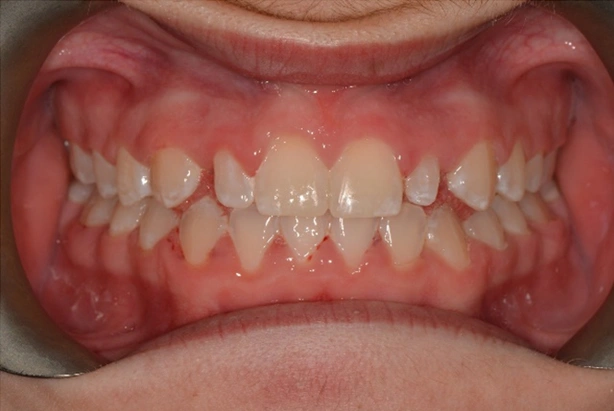

Peg Shaped Laterals

Diminutive lateral incisors are one of the most common problems we see. After careful assessment with patient, parent and referring dentist, it was decided to complete full fixed appliance treatment with space creation for composite buildups of the 12 and 22.

Alignment and occlusion were perfected and the patient referred back to dentist to approve of space distribution.

Appointments were coordinated so that all appliances were removed in the morning. Build-ups undertaken around lunch and final retainers issued by the end of the day.

A great result. With potential permanent indirect restorations after growth completed if needed.